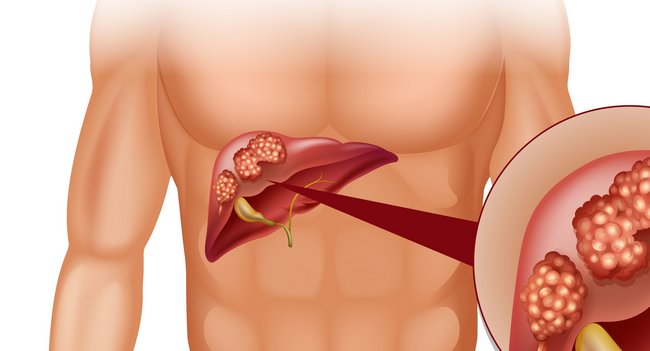

Гемангіома печінки – це пухлина, яка розташувалася в тканинах органу. Як правило, це доброякісне утворення. По своїй суті, гемангіома – це вроджена патологія, що з’являється при формуванні в ембріональний період печінки та її судин.

- Як правило, вона утворюється в правій частці;

Кавернозна

Кавернозний тип гемангіоми відрізняється тим, що складається з декількох порожнин, які виявляються заповненими венозною кров’ю. Кавернозна гемангіома печінки зростає через збільшення об’єму крові в організмі, зокрема, настає з-за вагітності. Розташовується, як правило, у правої частки печінки.

Такі пухлини здатні досягати великих розмірів і зливатися, займаючи практично всю частку. Іншими словами, людина, практично, позбавляється функціонально здорової частини органу, а з природною його роботою справляється частина.